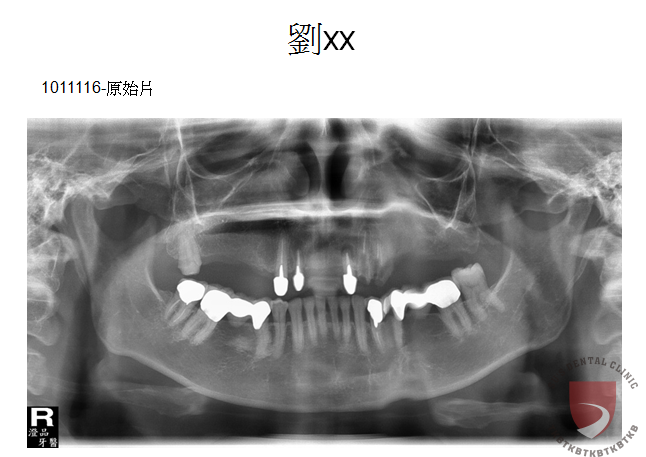

全口重建劉xx

成效因人而異,須遵從專業醫師指引